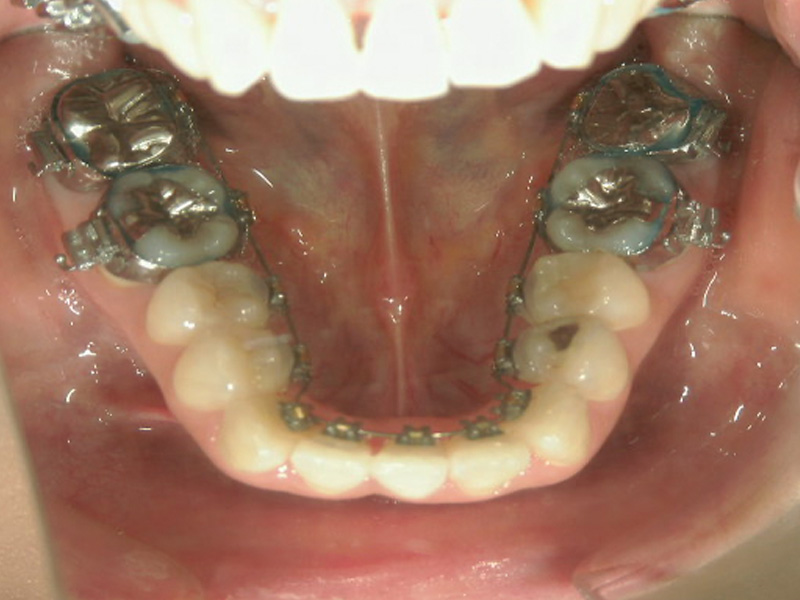

舌側矯正

目立たない

裏側に装置を装着するので周囲の目も気になりません。

違和感は大きい

裏に装置を付ける為、お口の中が狭くなります。装置になれれば不自由なく会話やお食事できます。